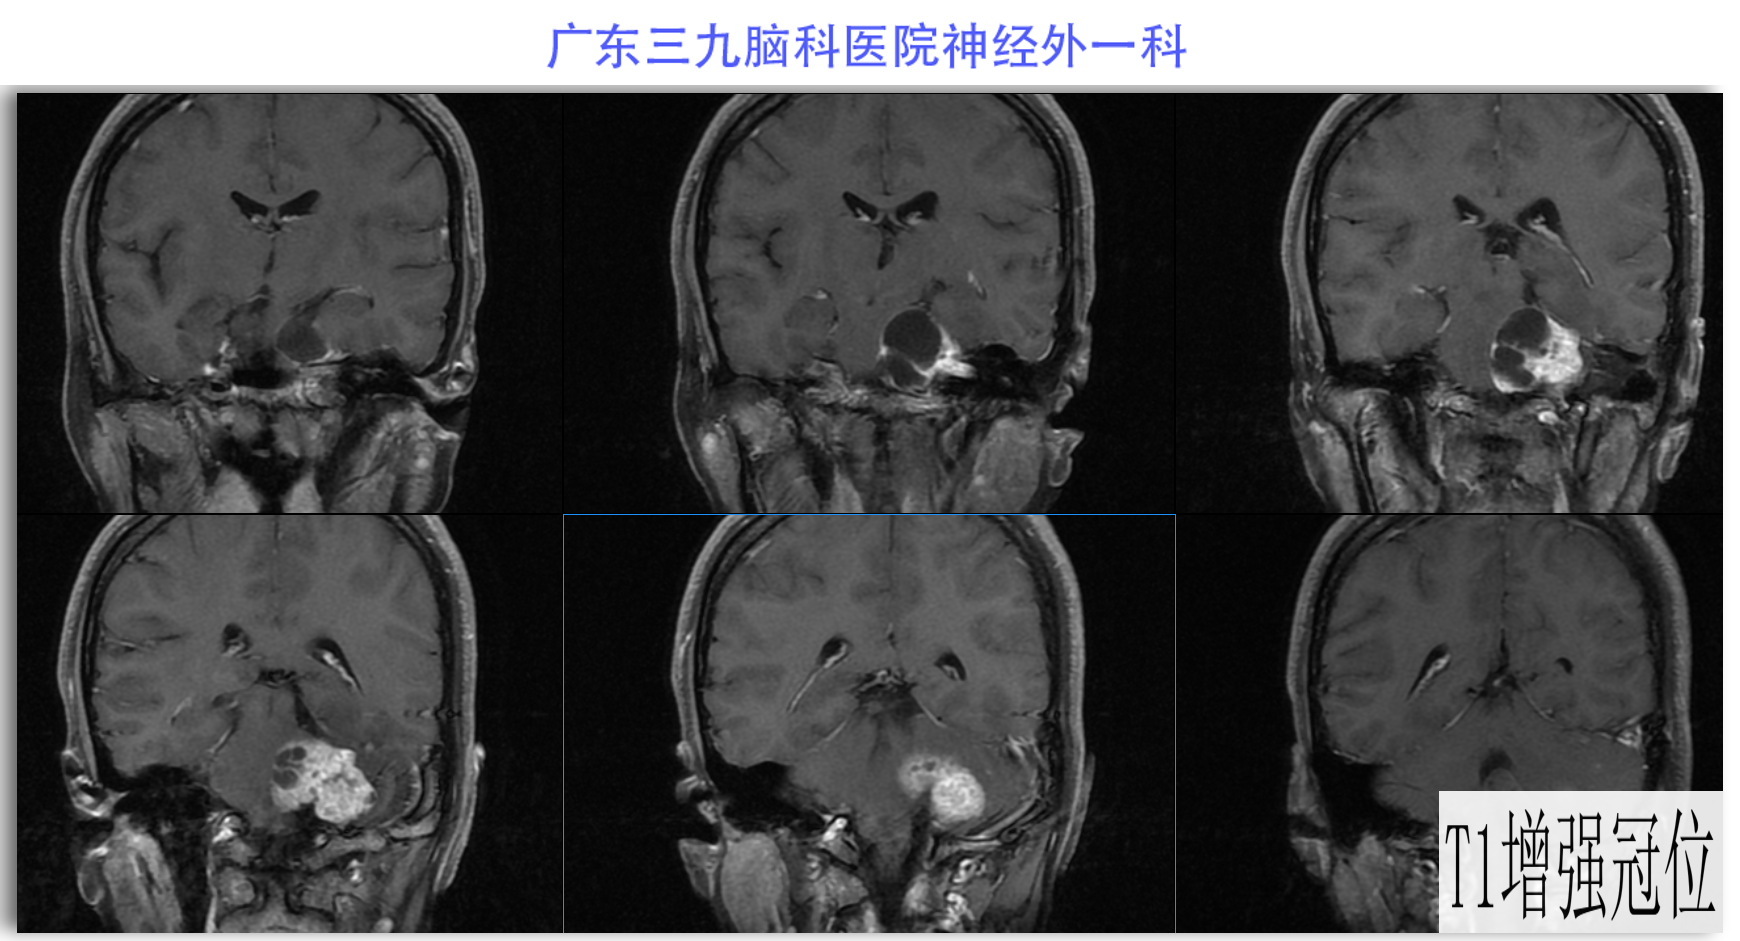

陈某某,女,41岁,因“左侧面部麻木3月余,吞咽困难半月余”于2024-02-17入院。患者3个月前出现左侧面部麻木,偶尔伴有头晕和左侧流泪,但没有听力下降或耳鸣。同时,患者也出现肢体乏力和行走不稳,但未接受任何治疗。半个月前,患者发现吞咽硬质食物稍有困难,同时左侧面部麻木加重。因此,前往当地医院就诊,并进行头颅MR检查,结果显示左侧CPA区存在占位性病变。为了进一步治疗,患者转诊至我院就医。术前检查显示:左侧角膜反射减弱,左侧鼻唇沟略微变浅,伸舌稍微右偏,咽反射迟钝。门诊诊断为“左侧巨大听神经瘤”,收治至我科进行住院治疗。手术过程顺利,术后患者恢复良好,面部轻度瘫痪与术前相同。术后病理检查结果确认为听神经瘤。